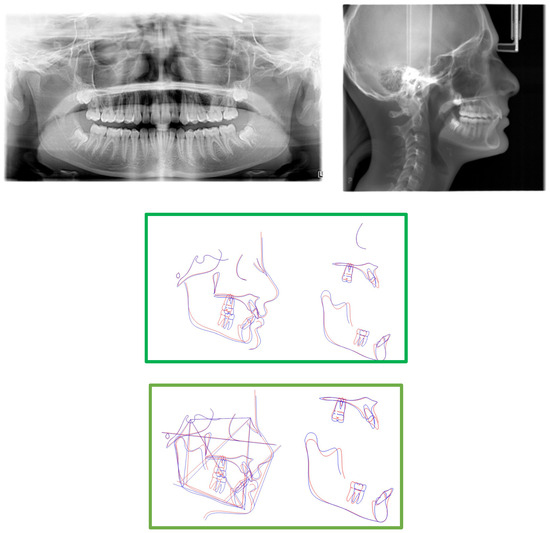

2. Presentation of Case Report

2.3. Treatment Progress

- Surgical exposure of the left mandibular canine using a diode laser (Doctor Smile, Lambda Spa, Brendola, Vi, Italy) for operculectomy and excision of fibromucous tissue. The corticotomy was performed using an ultrasonic piezosurgery system (Mectron Medical Technology, Carasco, Genova, Italy). A bottom (3M Unitek, Monrovia, CA, USA) was placed labially as close as possible to the canine’s coronal tip, combined with a metallic ligature and a cantilever (0.016 × 0.022 TMA, American Orthodontics, Sheboygan, WI, USA) without sutures (Figure 3a,b). The cantilever allowed for distal and buccal traction with light forces (1.7–2.8 ounces). A lingual arch was soldered (passive only on 31–32);

- Fixed multibrackets appliance (American Orthodontics Corp., Sheboygan, WI, USA, MBT prescription) were placed in the upper arch with 0.014 NiTi wire, bent back for controlling anchorage;

- After one month, a 0.016 NiTi wire was inserted in the upper arch;

- Fixed multibracket appliances were placed in the lower arch with a 0.014 NiTi wire, starting vertical traction of the canine. A bent back was used for controlling anchorage;

- After two months, the inferior left canine achieved a vertical position and reached its position in the arch. The bracket was replaced to adjust its axial inclination, and then a 0.016 NiTi wire was inserted;

- Before using stainless steel wire, a ligature from 16 to 26 and 36 to 46 for controlling anchorage was placed;

- 0.016 × 0.022 stainless steel wire was inserted in the upper and lower arches;

- 0.019 × 0.025 stainless steel wire was inserted in the upper and lower arches;

- Reverse Pin System” was placed on 13 and 23 to initiate class II biomechanics. Class II elastics (upper canines and first inferior molars) 3/8 4.5 ounces were used (Figure 3c). Class II elastics were used for 18 h every day;

- One year later, class I occlusion was achieved, and the class II elastics were used only during nighttime;

- Two years later, the appliance was deboned, and positioner retainers were given to the patient with the prescription to wear them every night.

| Measurement | Initial | Final | Norm |

|---|---|---|---|

| S^N^A | 85.2° | 85.5° | 81° |

| S^N^B | 81.3° | 81.8° | 79° |

| A^N^B | 4.2° | 3.7 | 2° |

| SN^Pog | 82.5° | 84.3° | 80° |

| S | 107.7° | 122.8° | 123° ± 5° |

| AR | 168.2° | 143° | 143° ± 6° |

| Go | 106.2 | 111.4° | 130° ± 7° |

| Upper gonial angle | 43.2° | 50° | 52°–55° |

| Lower gonial angle | 63° | 61.3° | 70°–75° |

| N^S^Ar^Go^Gn | 382.1° | 377.2° | 396° |

| Sn/Go-Me | 22.2° | 17.1° | 32° |

| SN | 67.6 mm | 69.7 mm | 71 mm |

| GoMe | 72.3 mm | 78.3 mm | 71 mm |

| S-Ar | 41.3 mm | 32.6 mm | 32 mm |

| Ar-Go | 33.1 mm | 53.8 mm | 44 mm |

| Dentoalveolar component | |||

| UI^SN | 116.15° | 113.37° | 102° ± 2° |

| LI^GOME | 109.72° | 114.5° | 90° ± 3° |

| Interincisal angle | 111.98° | 115.07° | 135° |